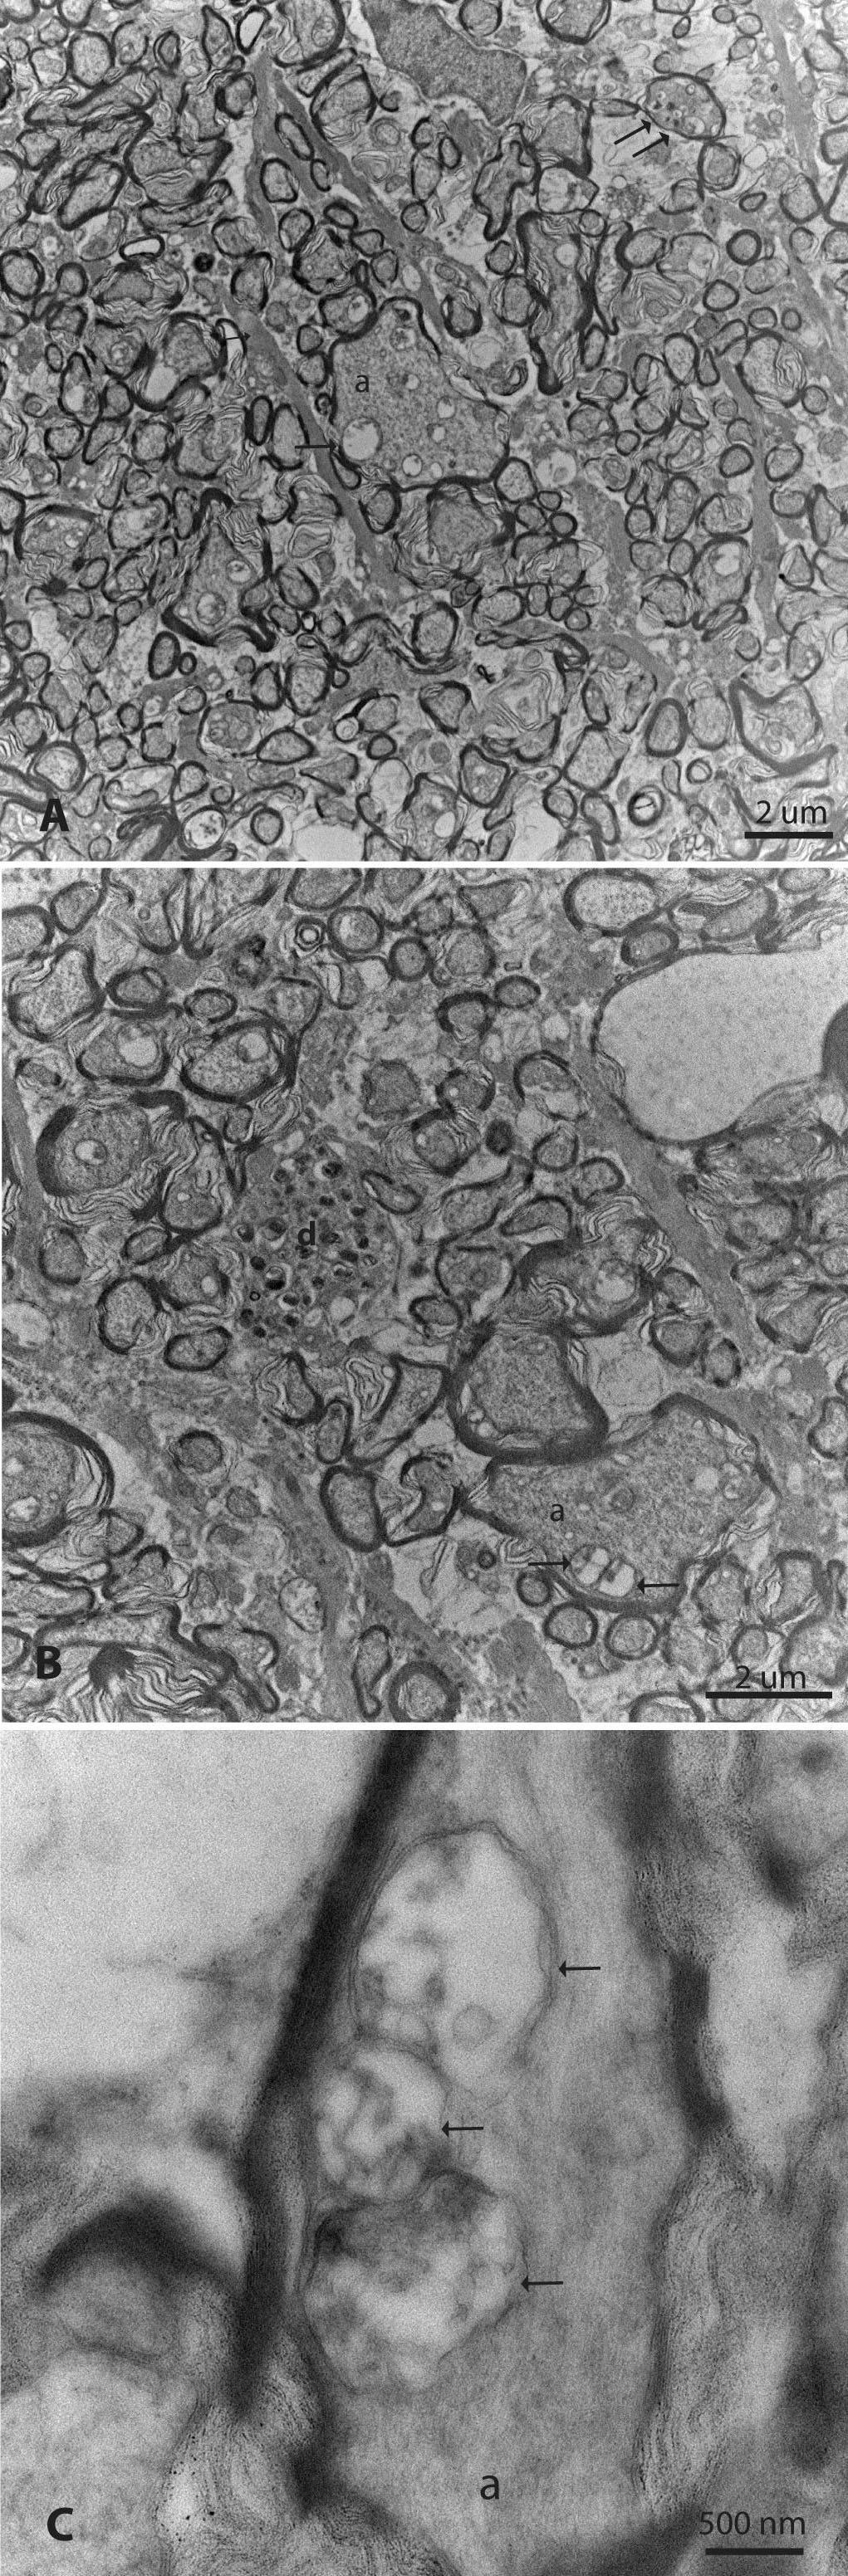

Figure 9. Mitochondria accumulate and fuse. A: Optic nerves from mutant ND4 MTS AAV injected eyes exhibited some large-caliber axons (a) with the accumulation of mitochondria (arrow) of varying diameters.

Electron-dense aggregations indicative of irreversible axonal degeneration were also evident (double arrows). B: In some swollen axons, two mitochondria were seen fusing (arrows). Irreversible axonal degeneration with intra-axonal electron

dense aggregations was evident in other axons (d). C: In another axon, three mitochondria (arrows) appeared to fuse.